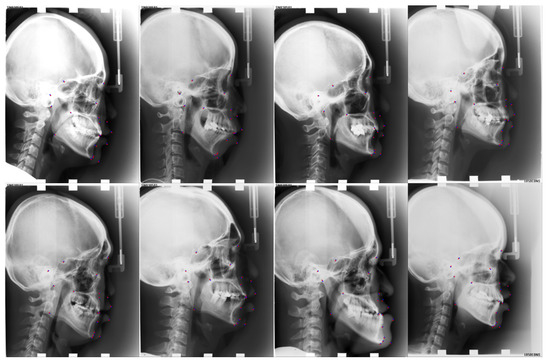

| Number | L1 | L2 | L3 | L4 | L5 | L6 | L7 | L8 | L9 | L10 |

| Anatomical Name | Sella | Nasion | Orbitale | Porion | Subspinale | Supramentale | Pogonion | Menton | Gnathion | Gonion |

| Number | L11 | L12 | L13 | L14 | L15 | L16 | L17 | L18 | L19 | |

| Anatomical Name | Lower incisal incision | Upper incisal incision | Upper lip | Lower lip | Subnasale | Soft tissue pogonion | Posterior nasal spine | Anterior nasal spine | Articulate |